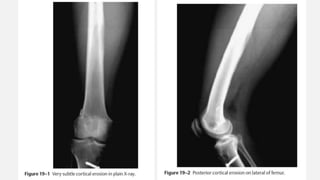

EWING’S SARCOMA FEMUR

• An otherwise healthy 20-year-old male developed a sudden increasing pain in his right

femur. The pain is so severe that he is unable to walk, needs crutches, and requires

high doses of narcotics. The pain awakes him from sleep. There is no history of

associated trauma. He has not noticed any pal- pable mass nor antecedent pain in his

right femur. Of note, he had a prior anterior cruciate ligament reconstruction on his

right side, but this procedure was done in the distant past and is unrelated to any of

his pain. He has actually had excellent rehabilitation from that procedure and tolerated

the procedure well. He has had no associated fever or chills. White count and

infectious laboratory work reveal normal sedimentation rate and C-reactive protein

(CRP). Anteropos- terior and lateral femur (Fig. 19–1 and Fig. 19–2) films show a lytic

lesion of the middiaphyseal region with a sun burst periosteal reaction. Magnetic

resonance imaging (MRI) (Fig. 19–3 and Fig. 19–4) revealed a soft tissue mass with a

right peritumoral inflammatory zone associated with it. The mass measures

approximately 5 × 4 × 3 cm. Computed tomogra- phy (CT) scan shows cortical

erosions as well. A chest CT also was performed, showing no obvious pulmonary

metastases. A bone scan was ordered as well (Fig. 19–5).

EWING’S SARCOMA FEMUR •An otherwise healthy 20-year-old male developed a sudden increasing pain in his right femur. The pain is so severe that he is unable to walk, needs crutches, and requires high doses of narcotics. The pain awakes him from sleep. There is no history of associated trauma. He has not noticed any pal- pable mass nor antecedent pain in his right femur. Of note, he had a prior anterior cruciate ligament reconstruction on his right side, but this procedure was done in the distant past and is unrelated to any of his pain. He has actually had excellent rehabilitation from that procedure and tolerated the procedure well. He has had no associated fever or chills. White count and infectious laboratory work reveal normal sedimentation rate and C-reactive protein (CRP). Anteropos- terior and lateral femur (Fig. 19–1 and Fig. 19–2) films show a lytic lesion of the middiaphyseal region with a sun burst periosteal reaction. Magnetic resonance imaging (MRI) (Fig. 19–3 and Fig. 19–4) revealed a soft tissue mass with a right peritumoral inflammatory zone associated with it. The mass measures approximately 5 × 4 × 3 cm. Computed tomogra- phy (CT) scan shows cortical erosions as well. A chest CT also was performed, showing no obvious pulmonary metastases. A bone scan was ordered as well (Fig. 19–5). Orthopedic Oncology by Ernest Conrad Thieme